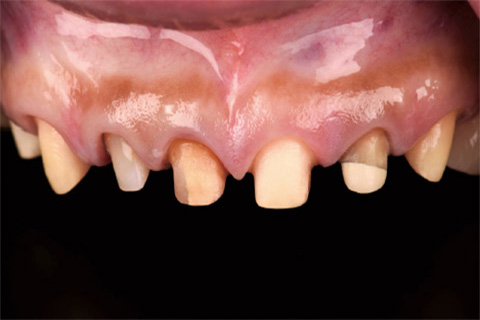

術後3ヵ月で2nd Provisional Restorationを装着した状態を示す(図19、20)。6前歯の左右対称な歯頸線の位置と、健全な歯周組織が認められた。その後、歯周組織の安定後に、最終形成を行った(図21)。最終印象前の歯周組織の咬合面観を示す(図22)。側切歯と犬歯の歯頸部歯肉の厚みの左右差に注目して頂きたい。初診時に右側の歯頸線の位置が根尖側よりだったのは、右側の辺縁歯肉に厚みがあったことによる。

図20 術後3ヵ月の前歯部側方面観。歯周組織は安定している。

図21 歯周組織の安定後に、最終形成を行った

図22 歯周組織の咬合面観。歯頸部歯肉の厚みの左右差に注目して頂きたい。